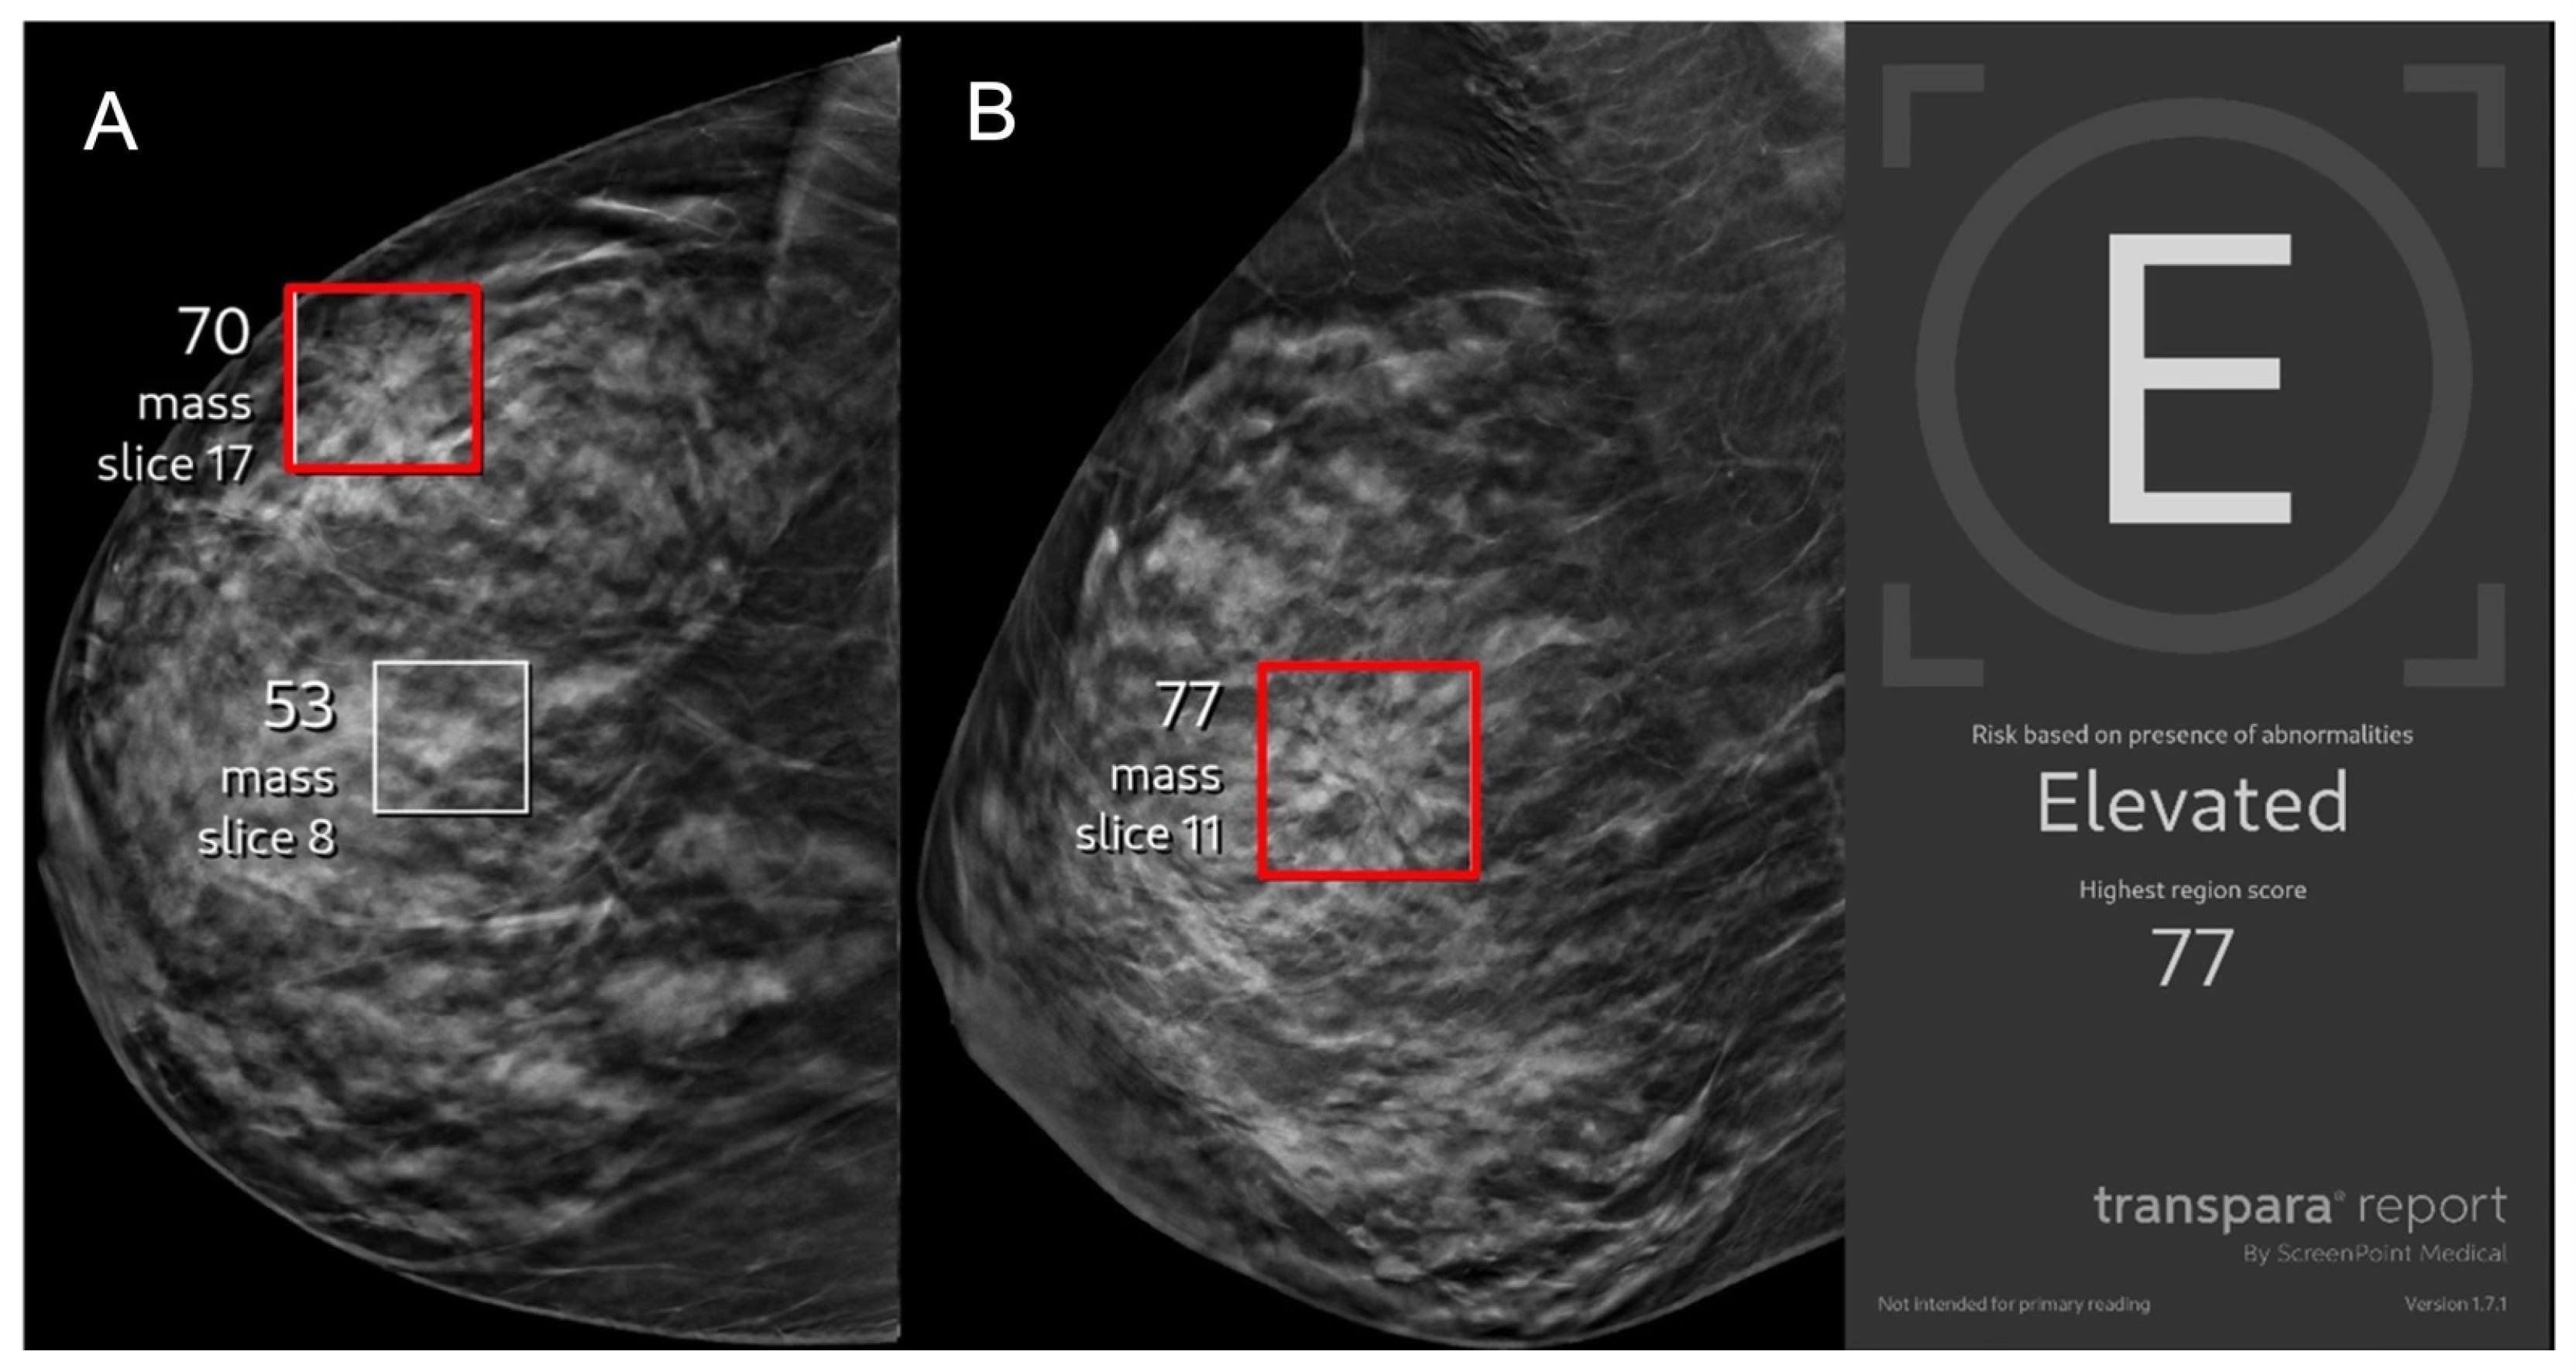

Follow-up of the largest randomized trial of AI in medicine was reported a week ago. The Mammography Screening with Artificial Intelligence trial (MASAI) randomized trial in Sweden of more than 105,000 women compared the interpretation by two radiologists with one radiologist with AI support. This represents the culmination of several years of intensive research exploring the potential role of deep learning AI to improve the accuracy of interpreting mammograms beyond that of radiologists. In this edition of Ground Truths I will explain why it is time to adopt AI as an adjunct for all mammograms, with attention to (1) improved accuracy for detection with reduced workload; (2) prevention of breast cancer; and (3) risk of heart disease (yes, you read that right). But, of course, there are obstacles for implementation which I’ll also review.

The National Cancer Institute estimates that 20% of breast cancers are missed by mammograms, leaving plenty of room for the potential of AI to help.

Since that time, retrospective studies of various AI algorithms were reported on a frequent basis. Then, in 2023, a real world of medicine study in Hungary with the Kheiron algorithm was published in Nature Medicine. Like MASAI’s design, comparing 2 radiologists vs 1 (or 2) plus AI, it found enhanced detection of cancer, 83% of which are invasive.